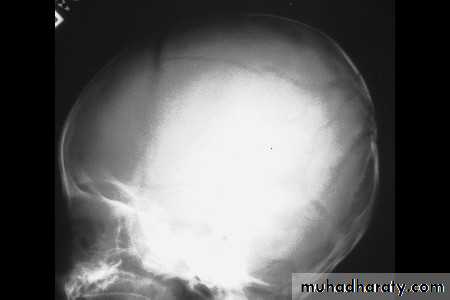

كسور الجمجمة، انظر الى الصورة القادمة

20 نيسان، 1315